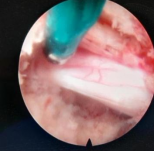

4.微创脊柱内镜技术:PELD+UBE+OSE

脊柱内镜技术是一项开展较早的脊柱外科微创技术,与传统开放手术相比,它是借助天然解剖间隙建立微创工作通道,解除神经压迫;对椎旁肌肉损伤较小,且能够最大程度地保留完整的脊柱结构,维持了术后脊柱的稳定,具有创伤小、出血少、恢复快、并发症少、疗效确切等优点。目前已开展椎间孔镜下髓核摘除术,单侧双通道脊柱内镜(UBE)下椎管减压术并处于区域内领先水平。我院在江苏省内率先开展了单孔分体式脊柱内镜技术(OSE),处国内领先水平。